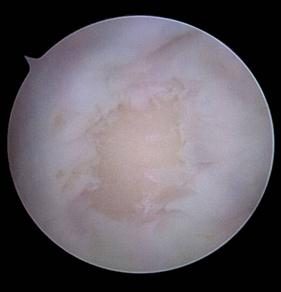

|

Fig. 1.16 Imagine artroscopica - fractura recenta la nivelul platoului tibial, se observa meniscul fara leziuni evidente si o leziune condrala la nivelul condilului femural |